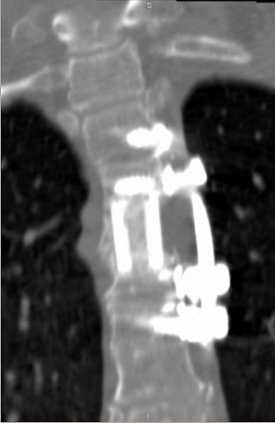

CT also can aid in finessing corpectomy procedures done to treat burst fractures. El-Khoury described an emergency case in which imaging saved the patient from further disaster (images A-F below).

"This patient arrived at the ER paraplegic. We see a little compression here, but we cannot see the entire problem. When we do CT, we see that this is a huge burst fracture. This was fairly acute. (The surgeon) did a corpectomy, which we followed with CT. He put a graft, two levels above and below the fusion," El-Khoury said. "When we looked closely at the CT, we noticed that the lower two screws are sitting and indenting the aorta. We called the surgeon and told him this: 'You have a situation in which you have metal screws pulsating against an aorta, and you know who is going to win in the end.' So the surgeon did an angiogram. The surgeon went in, removed the screws, and fused the patient from the back."